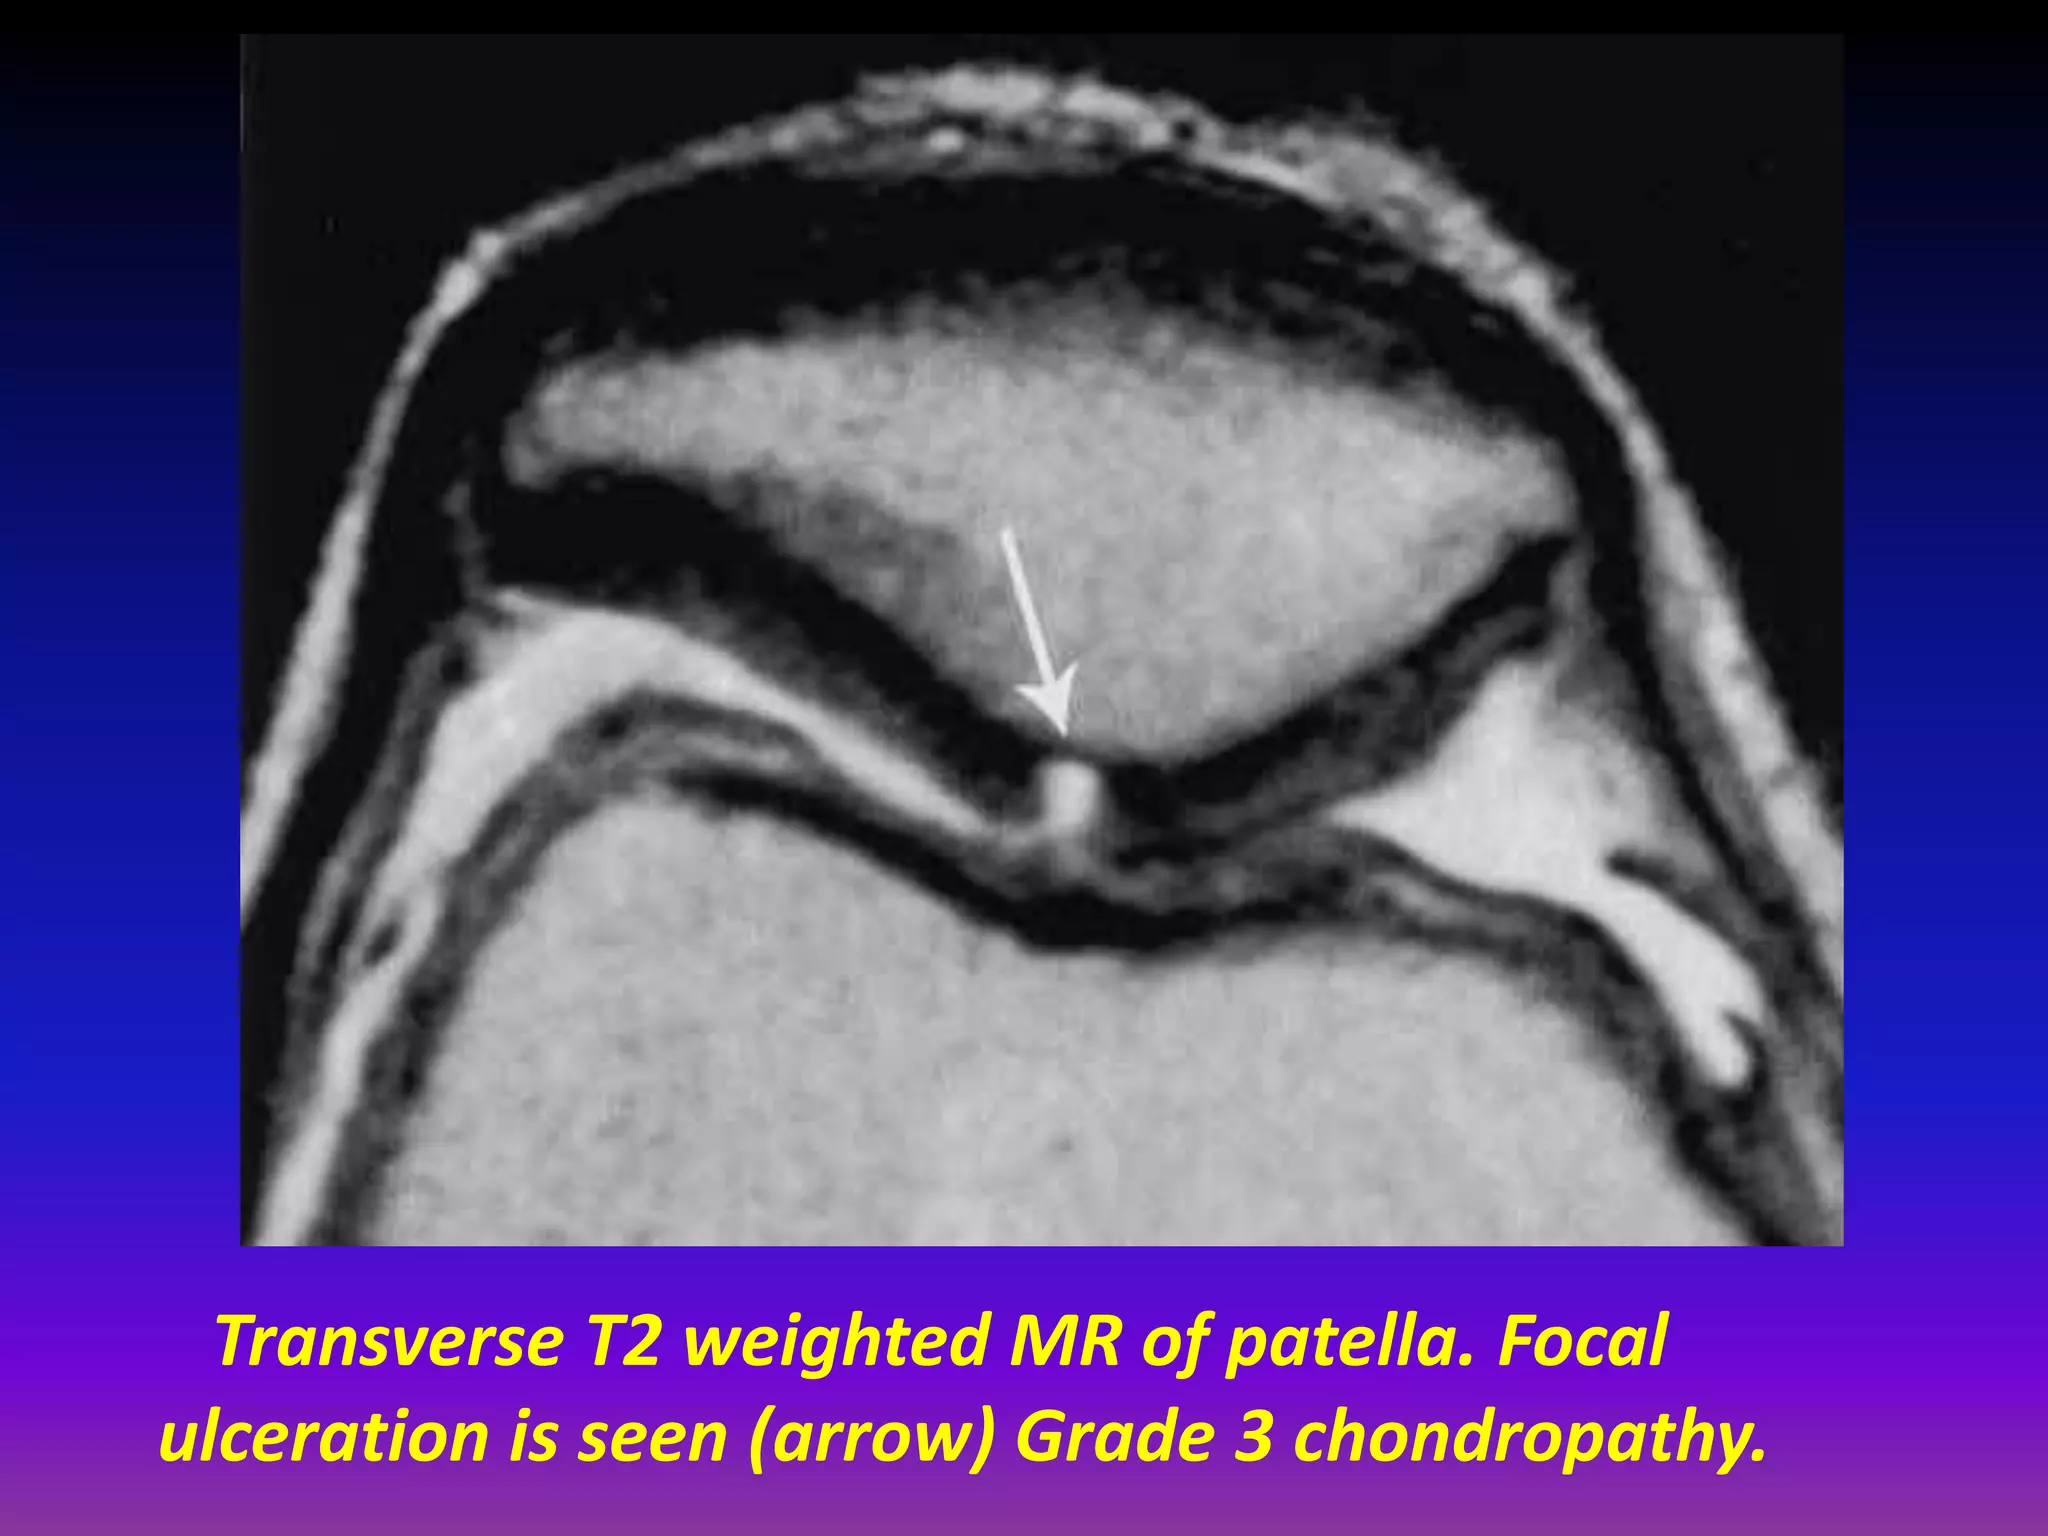

Transverse T2 weighted MR of patella. Focal

ulceration is seen (arrow) Grade 3 chondropathy.

Transverse T2 weightedMR of patella. Focal ulceration is seen (arrow) Grade 3 chondropathy.

Transverse (T2 fatsat) weighted MR of patella. Focal ulceration is seen (arrow) Grade 3 chondropathy.